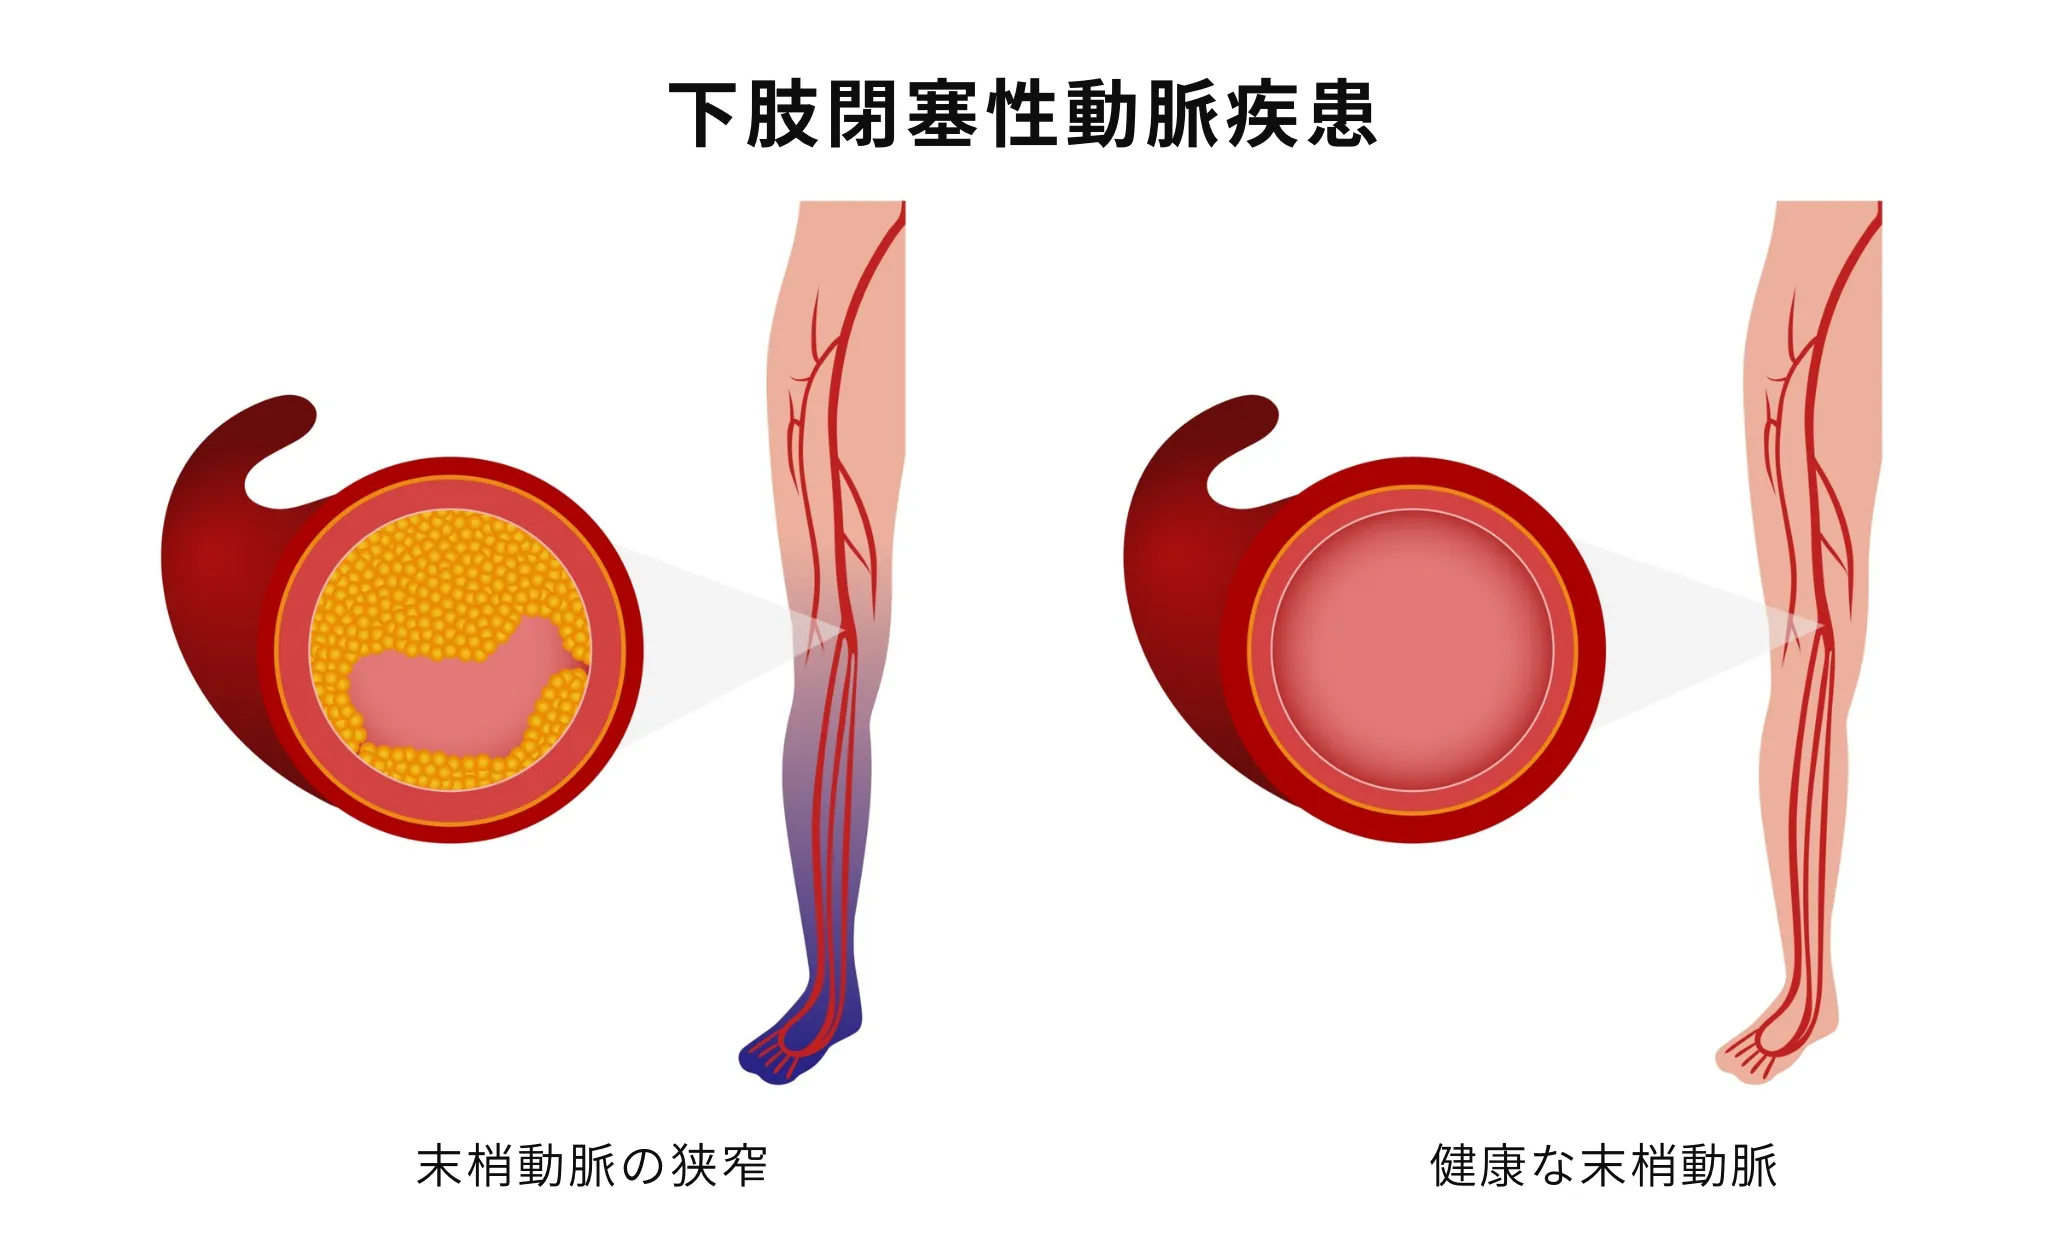

下肢閉塞性動脈疾患(LEAD)

下肢閉塞性動脈疾患(LEAD)は、末梢動脈疾患(PAD)の中でも下肢に発症したものを指し、主に足の動脈が動脈硬化により狭くなったり詰まったりすることで、血流が不足する病気です。(従来、閉塞性動脈硬化症(ASO)と呼ばれていた病態に相当します。)

歩行時に足のだるさや痛みが出現し、休むと治まるのが特徴的な症状です。進行すると、安静時にも痛みが現れたり、足に傷ができて治りにくくなったりします。重症の場合は、組織の壊死に至ることもあります。

糖尿病、高血圧、脂質異常症、喫煙が主なリスク因子であり、これらの疾患を持つ方は特に注意が必要です。また、心臓や脳の血管にも動脈硬化が進行していることが多く、心筋梗塞や脳卒中のリスクも高まります。

下肢閉塞性動脈疾患では、初期には歩行時の足のだるさや痛み、しびれなどを生じます。特徴的なのは一定の距離を歩くと足が痛くなり、休むと数分で治まる症状があることです。階段を上る、坂道を歩くといった動作で症状が出やすく、進行すると歩ける距離が徐々に短くなります。

足の冷感、足の色が青白くなる、足の傷が治りにくい、足の爪が厚くなるといった症状も現れます。さらに進行すると、安静時にも足が痛む(特に夜間)、足に潰瘍ができる、足の指が黒くなる(壊死)といった重症の症状が出現します。

治療の基本は、動脈硬化の進行を防ぐことです。最も重要なのは禁煙で、喫煙を続けると治療効果が著しく低下します。高血圧、糖尿病、脂質異常症の適切な管理も必須です。

薬物治療では、抗血小板薬により血栓形成を予防します。下肢閉塞性動脈疾患では、血流改善薬により、歩行可能距離の延長が期待できます。